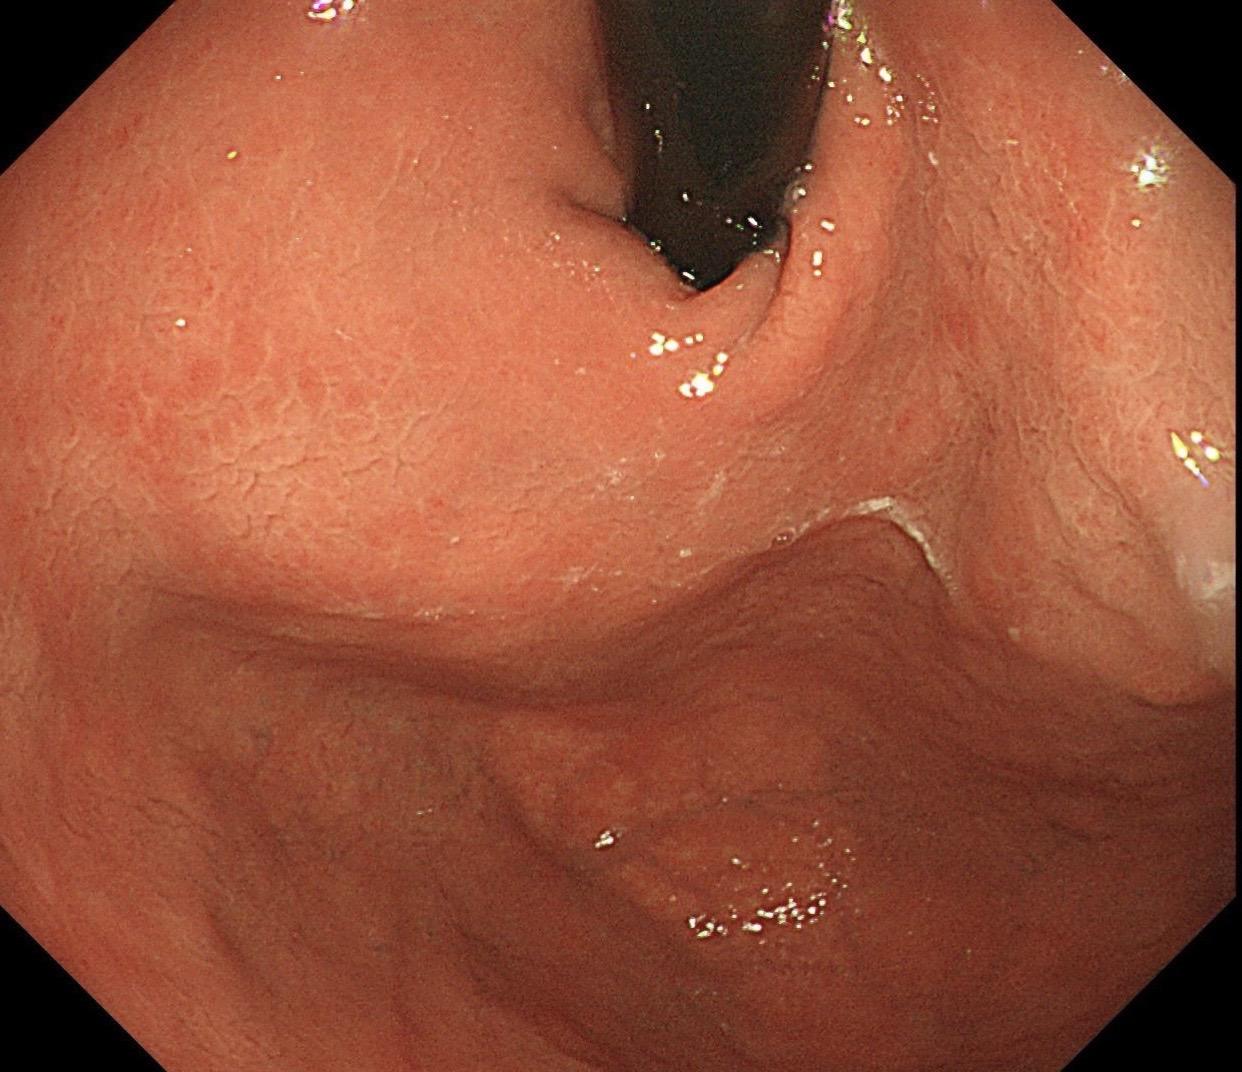

男,40岁,胃双发褪色调病变。慢性胃炎复查,3年前胃镜未见异常,Hp阳性背景,萎缩不明显,胃体下部大弯见一褪色调病变,浅凹陷,5mm左右,换用放大内镜观察,表面结构缺失,血管异型明显,未分化可能性大……胃窦后壁见一白斑,无高度差,NBI浅茶色,放大草草看了下,似有边界,IP增宽,活检待病理……小哥哥胖得几乎没脖子,腹式呼吸太明显~😖